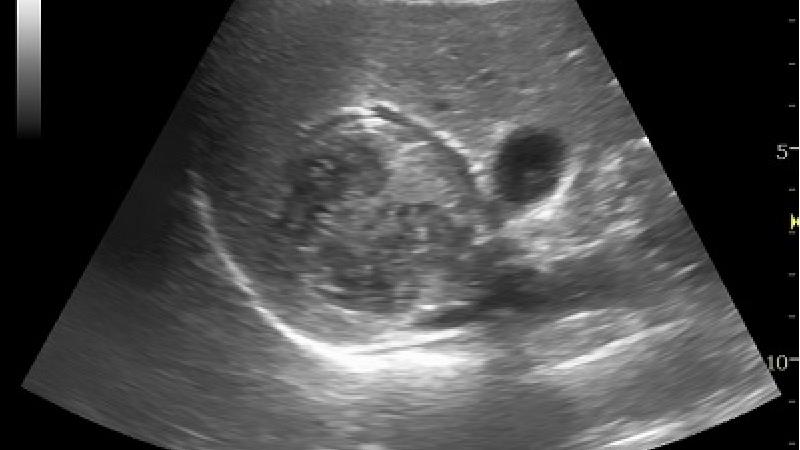

در این مرحله بیماری با استفاده از تست هایی نظیر تشخیصی و افتراقی و روش های رادیوگرافی، سونوگرافی و سی تی اسکن شناسایی شود.